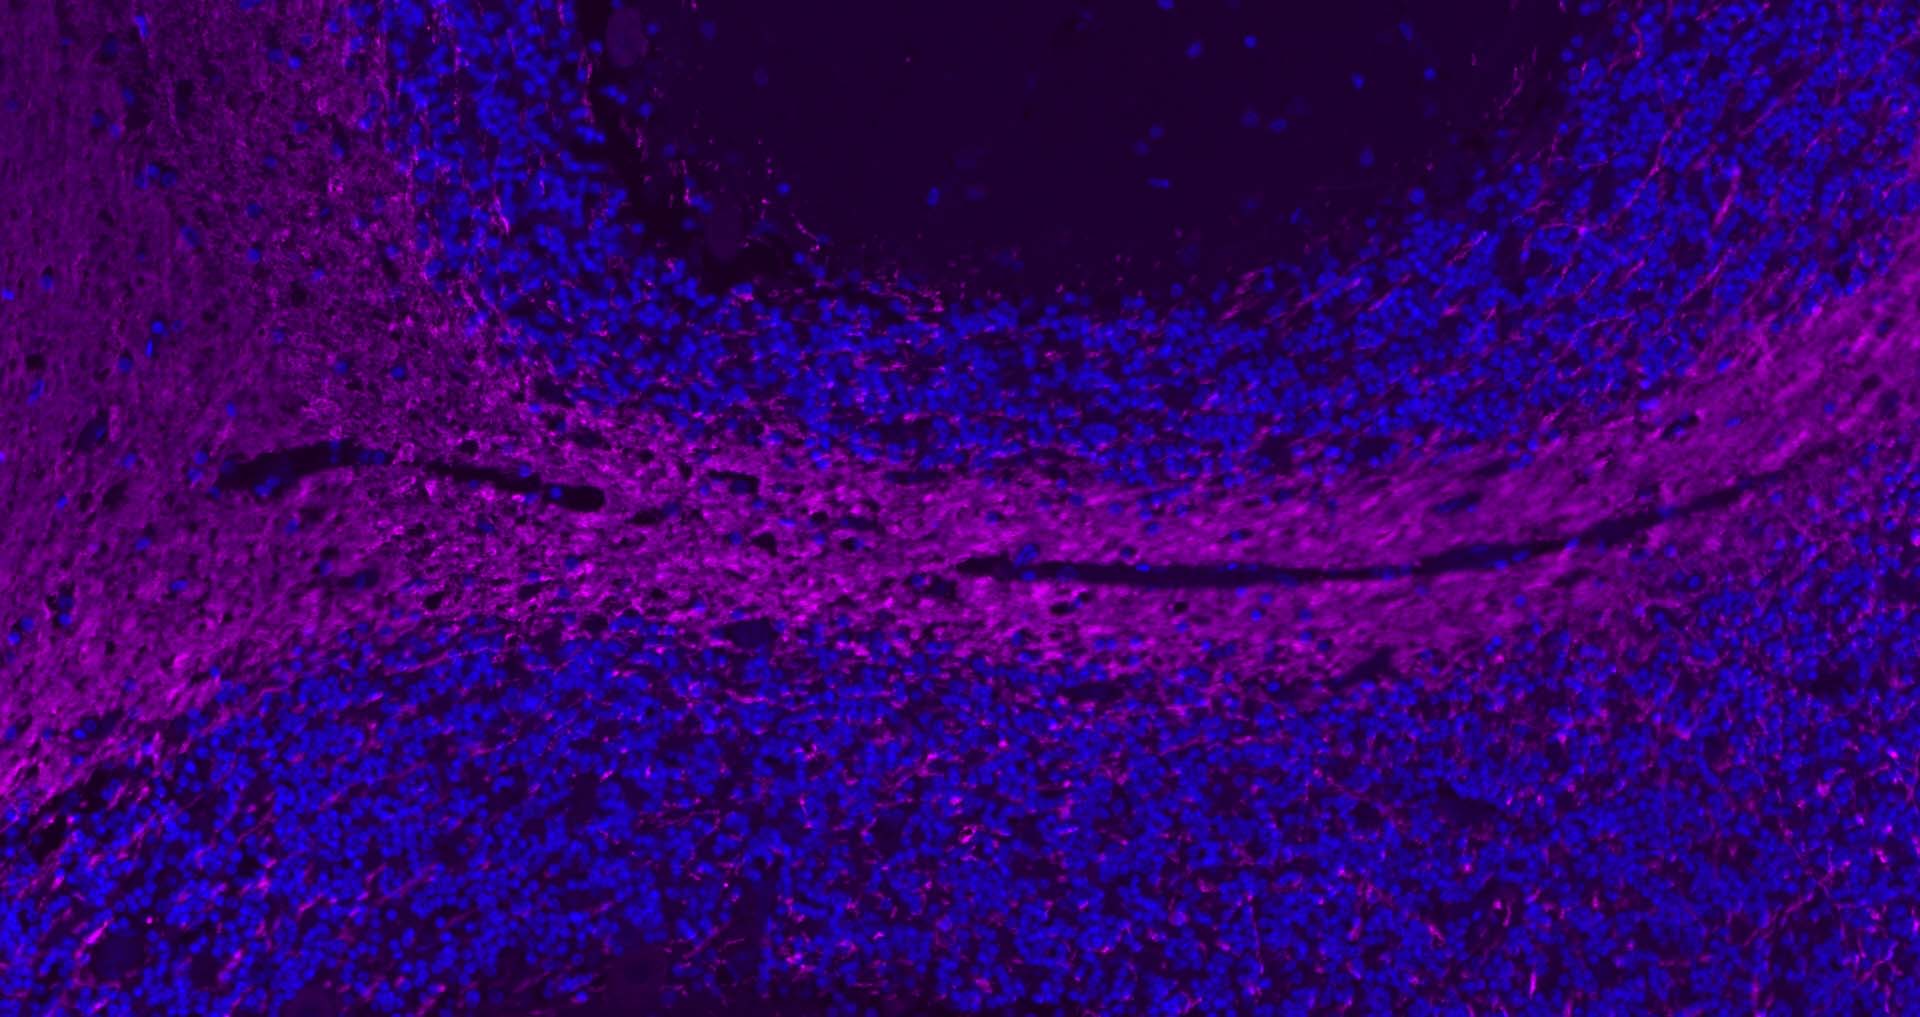

The protein encoded by the classic MBP gene is a major constituent of the myelin sheath of oligodendrocytes and Schwann cells in the nervous system. However, MBP-related transcripts are also present in the bone marrow and the immune system. These mRNAs arise from the long MBP gene (otherwise called "Golli-MBP") that contains 3 additional exons located upstream of the classic MBP exons. Alternative splicing from the Golli and the MBP transcription start sites gives rise to 2 sets of MBP-related transcripts and gene products. The Golli mRNAs contain 3 exons unique to Golli-MBP, spliced in-frame to 1 or more MBP exons. They encode hybrid proteins that have N-terminal Golli aa sequence linked to MBP aa sequence. The second family of transcripts contain only MBP exons and produce the well characterized myelin basic proteins. This complex gene structure is conserved among species suggesting that the MBP transcription unit is an integral part of the Golli transcription unit and that this arrangement is important for the function and/or regulation of these genes.

| IHC-F | Human, Mouse, Rat | Rabbit, Pig, Sheep, Cow, Dog, Horse | 1:500-2000 |